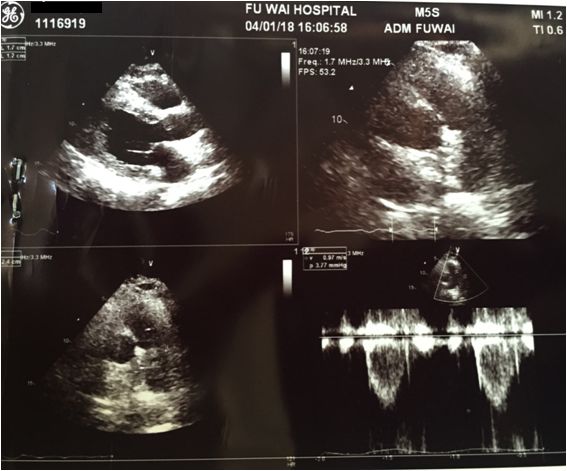

LA 41mm,LV47mm,EF 65%

左房扩大,室间隔及左室各壁中下段增厚以心尖部增厚为著,最厚处约25mm

室壁回声粗糙,呈斑点样改变,心肌纹理排列紊乱,运动减低,收缩期左室中部内径狭窄

多普勒检查:左室中部可见收缩期高速血流,最高压差80mmHg,收缩期左房内可探及源于二尖瓣口的少量返流信号